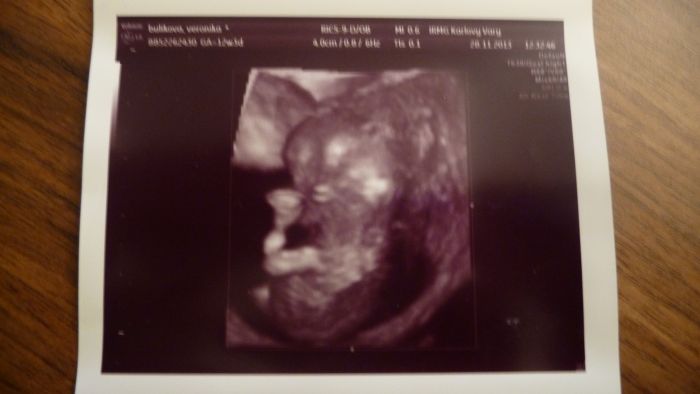

jeste pridavam foto nasi princezny a dneska jsem se rozhodla a bude se jmenovat Ellen.....tata bude mit radost az na kost a moje sestra taky, ti dva totiz jmeno vymysleli

Marti, krásná fotečka!

[397014] Martasku a v kolikatem jsi? Ja jsem 12+4 a nemam z dneska tak hezkou fotku. 3D úplne nepoznatelny a normální docela pěkný, ale třeba nozicky nejdou v podstatě videt.

Ahojte těhulky, tak jsem dnes byla na screeningu, KONEČNĚ... ALE... čekám prý flegmatické spací mimčo

Doktor do mě bušil, musel mě vyšetřit vaginálně a mímo pořád spinkalo, vždy se jen zavrtělo, jako že nech mě a zase spinkalo. Vypadá prý vše ok, krev budou volat jen pokud něco objeví. Tak snad to bude také OK. Jinak máme 4,64 cm a Dr. mi řekl, že nejspíš nebudu v tom 12tt ale asi v 10tt. Tak nevím. Posune se mi TP, tak příští pondělí jdu na kontrolu k mé Dr. tak písnu. Srdíčko jsme s přítelem slyšeli a bylo to úžasné. Pohlaví nevíme, prý se nám správně nenatočila a je ještě brzy. Ale dva známí tatínkové na to koukali a bylo jim hned jasno. Viděli holčičku.

Tak snad se chlapáci taťáci nemýlili. Přítel byl na screen. celou dobu semnou a byl nadšený, nejvííc ze zvuku srdíčka. Mám 4 fotky a to jen proto, že to malé jen spalo, tak ho Dr. aspoň fotil. Bylo nádherné vidět toho tvorečka, jak si dává ručičky k obličeji a za hlavu. Jednu nožičku mělo nataženou a druhou pokrčenou. Jsem šťastná. Gratuluji maminám co ví už pohlaví.